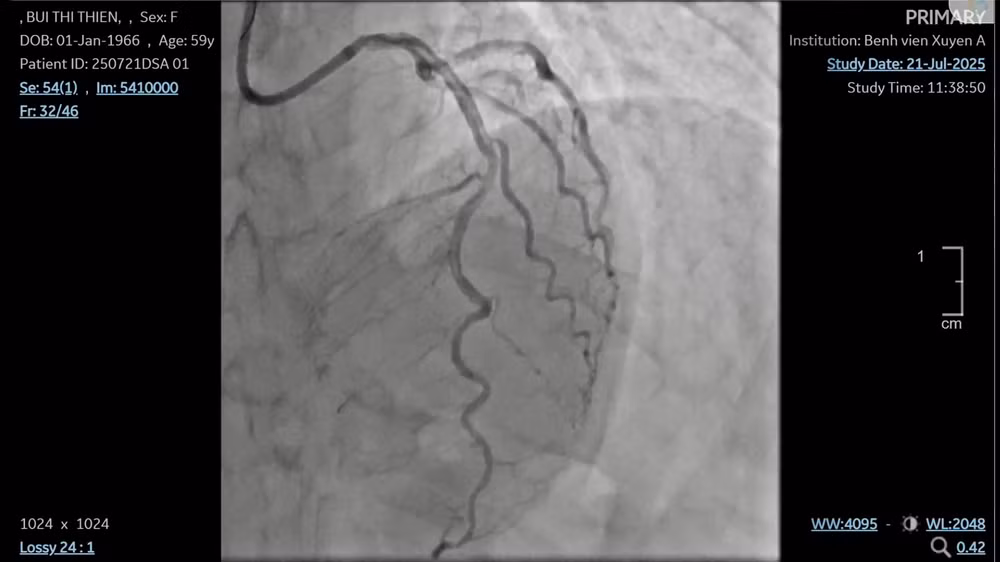

Kết quả kiểm tra cho thấy, nhánh động mạch vành trái hẹp nặng, động mạch vành phải tắc gần như hoàn toàn, chứa nhiều huyết khối. Đây chính là nguyên nhân khiến dòng máu nuôi tim bị cắt đứt đột ngột.

Mạch máu sau khi đặt stent.